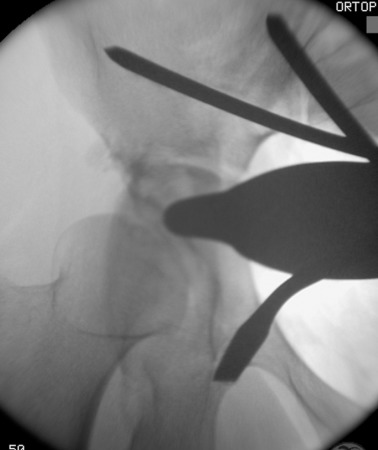

Prior to conducting the osteotomies, the greater sciatic notch, supraacetabular region, pubic rami, and quadrilateral surface were exposed, and the distances were measured as described by Shiramizu et al.15 The first osteotomy was performed on the supra-acetabular region and the iliac wing, from the pectineal line and aiming 1–2 cm distal to the medial of the anterior superior iliac spine (ASIS) (Fig. 4 ). The second osteotomy was performed on the posterior colon of the acetabulum, under fluoroscopic guidance with a 45° oblique view of the iliac. This osteotomy was from the pectineal line to the inferior ischium with an angle of 130° to the first osteotomy, leaving approximately 1 cm of bone posterior to the osteotomy line to preserve the posterior colon, as described in previously conducted anatomical studies (Fig. 5 ).15 The third osteotomy was performed on the pubic arm near to the acetabulum (Fig. 6  ;  Fig. 7 ). And the last osteotomy was performed on the distal ischium, parallel to the inferior acetabular rim (Fig. 8 ). Each stage of the operation was conducted under fluoroscopic control to ensure that the osteotome did not penetrate the joint. By twisting the osteotome under fluoroscopic guidance, it was ensured that the fragment was completely free. After completing the osteotomies, the acetabular fragment was medialized and rotated anterolaterally using a spike-tipped pusher. An anterolateral repositioning of approximately 20° was achieved under fluoroscopy. After the correction, the osteotomy was fixed with 2 or 3 3.5-mm screws (DePuy Synthes, Bettlach, Switzerland), which were inserted percutaneously from the iliac crest to the supraacetabular area, using 0.5- to 1-cm skin incisions.

Posterior colon osteotomy.

Fig. 5.